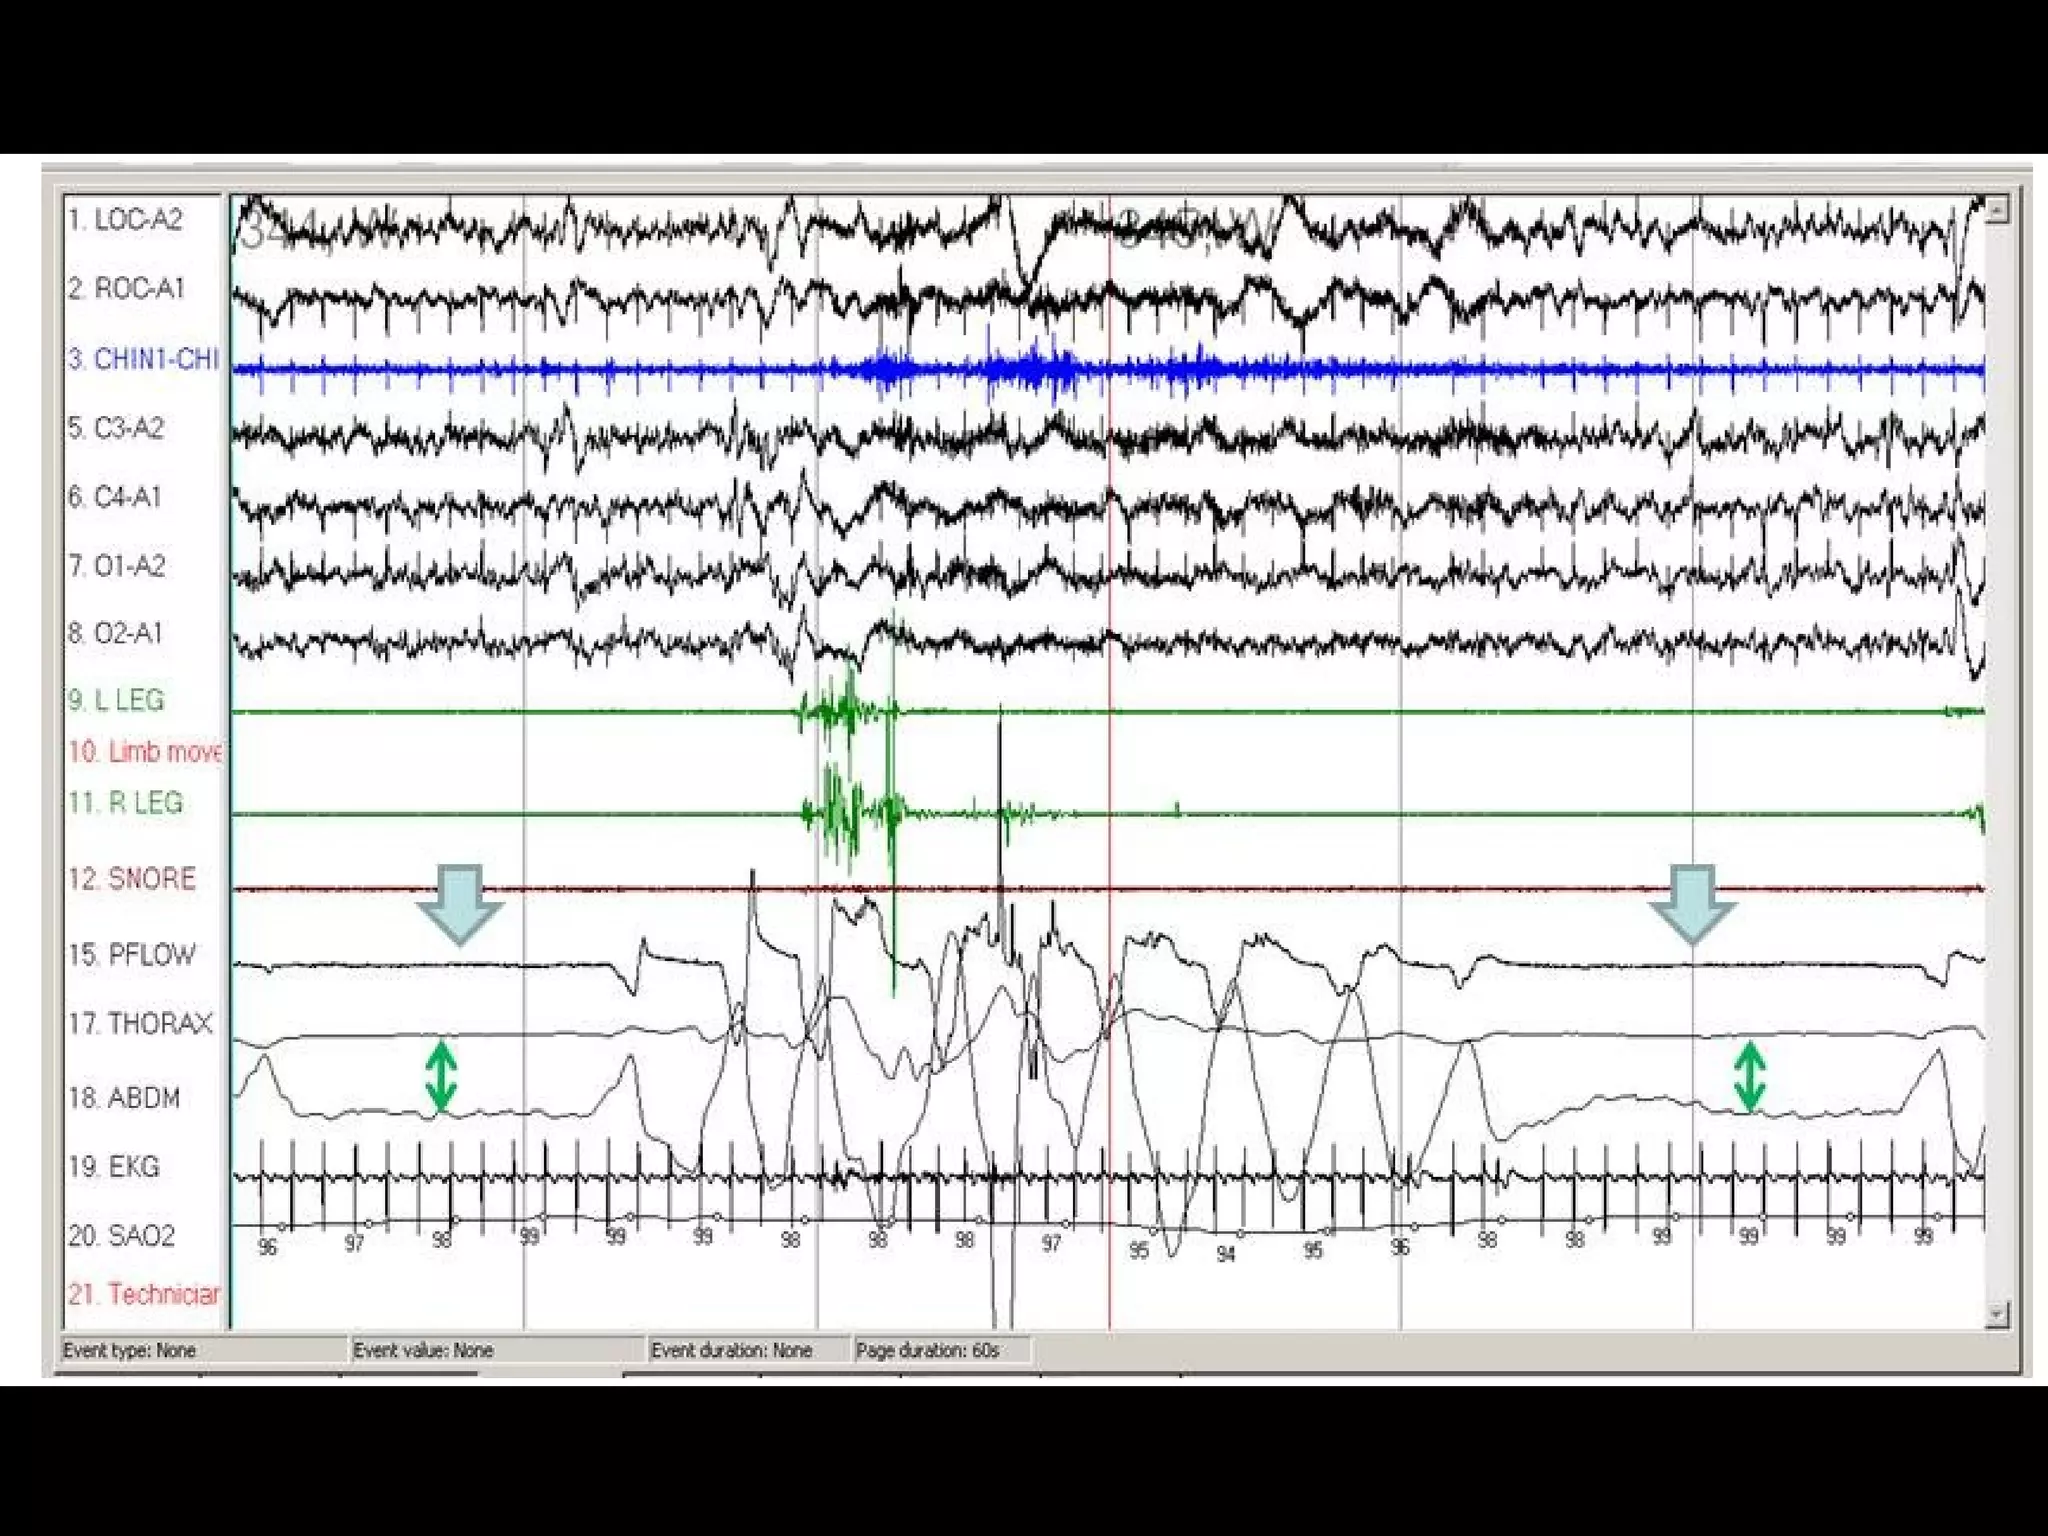

#43 Obstructive sleep apnea. Note the absence of flow (red arrow) despite paradoxical respiratory effort (green arrow).

#44 Comparison of a central apnea (box) and obstructive apnea (circle).

#45 Central sleep apnea (thick areas). Note the absence of both flow and respiratory effort (green double arrows).

Central apnea is the cessation of airflow for at least 10 seconds with no respiratory effort

#46 Mixed sleep apnea. Note that the apnea (orange arrow) begins as a central apnea (effort absent; red double arrow) and ends as an obstructive apnea (effort present; green double arrow). Note the arousal (blue arrow) that terminates the apnea and the desaturation (purple arrow) that follows